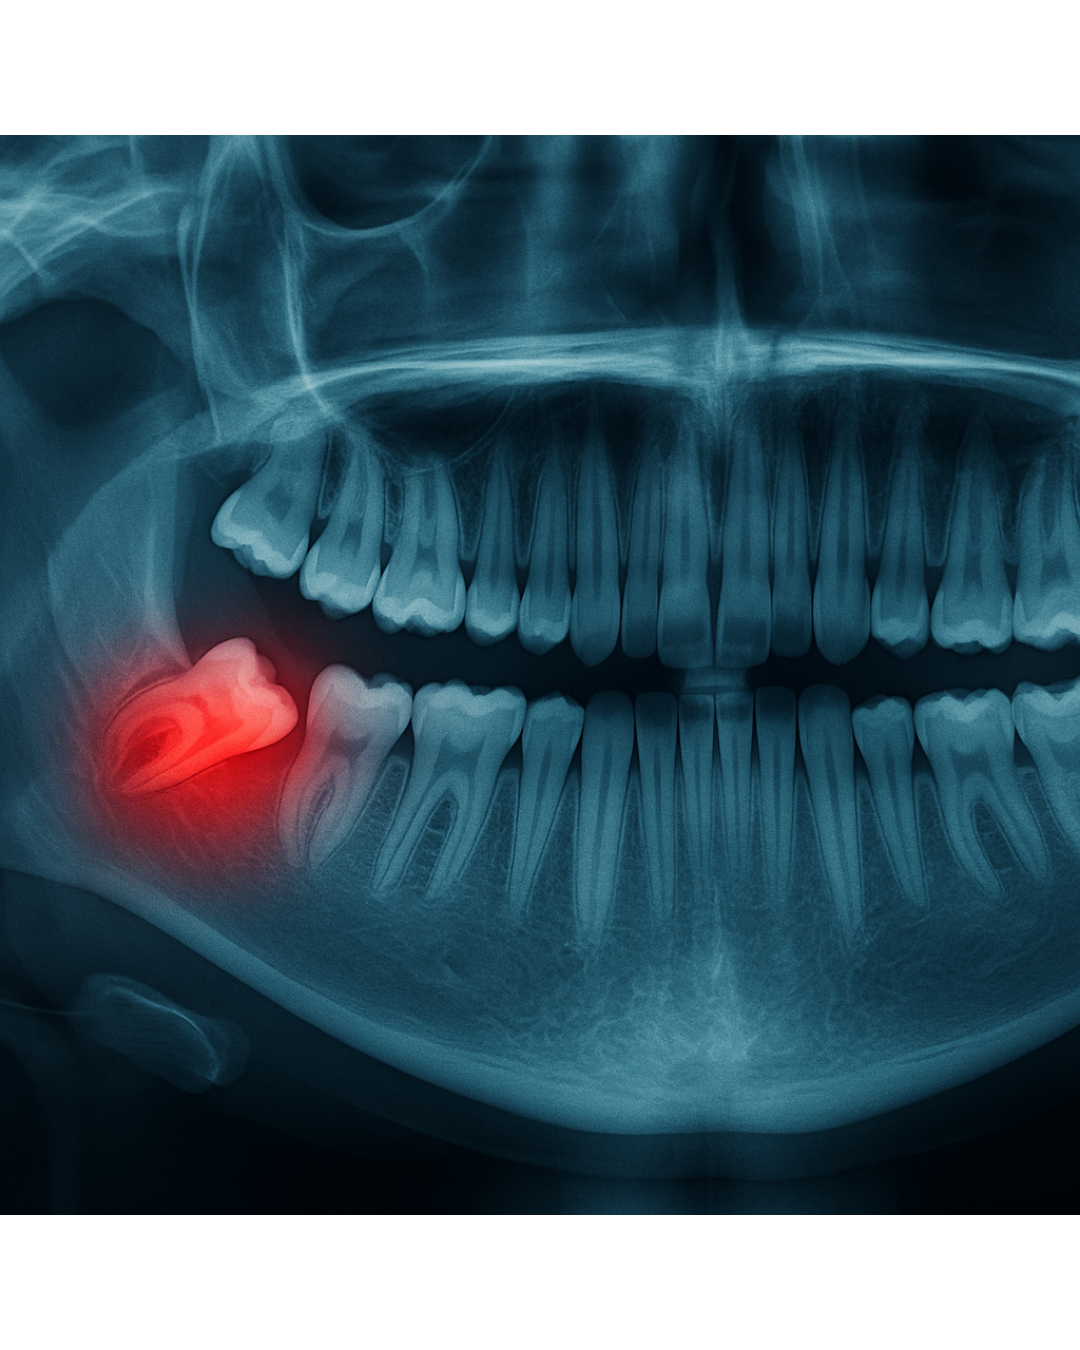

Wisdom Tooth Extraction

Simple extractions of teeth visible in the mouth and that can be removed without a surgical approach.

Dr Nicolas uses gentle techniques to ensure that the process is as quick and comfortable as possible.

They are usually carried out under local anaesthetic.